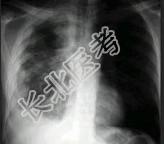

- 单项选择题男,40岁, 胸痛胸闷2月,胸片如图, 最可能的诊断为 ( )

A、右侧恶性胸膜间皮瘤

B、右侧胸腔积液

C、右侧包裹性积液

D、右侧良性胸膜间皮瘤

E、右侧胸膜增厚